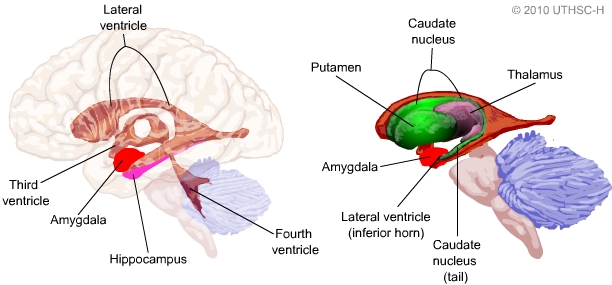

Amygdala: What It Is and What It Controls

Know Your Brain: Amygdala

Amygdala Function and Location

Limbic System: Amygdala (Section 4, Chapter 6) Neuroscience Online

Amygdala: Anatomy, Location, and Function

Schematic drawing illustrating the location of the amygdala and

Limbic System: Amygdala (Section 4, Chapter 6) Neuroscience Online

The Limbic System